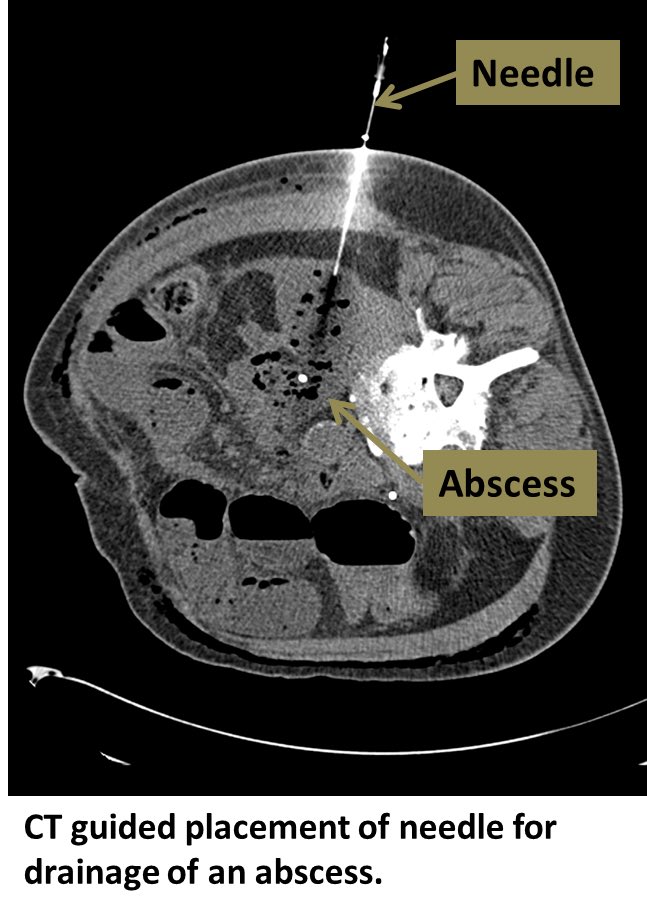

Abdominal collections: (General Rules)

Percutaneous drainage if size > 4cm

IV AB if smaller

O.R if unstable